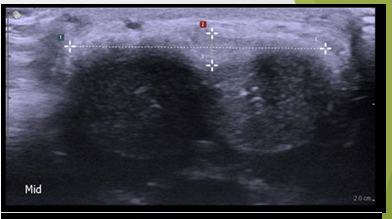

Dorsal plaque with no calcification. No acoustic shadowing present

Dense calcified dorsal plaque. Red arrow indicates acoustic shadowing